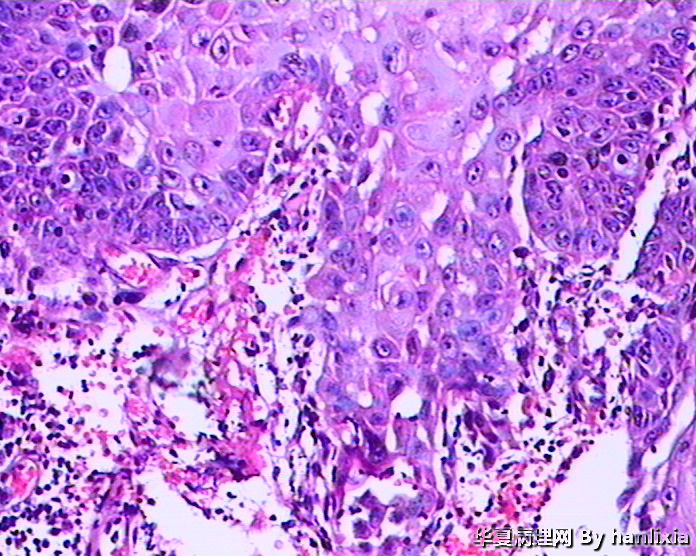

男性患者,50岁,发现面部皮肤(耳旁)肿物一年余,色黑。

高分化鳞状细胞癌

高分化鳞癌可能,也可能AK基础上发展而来的浅表型鳞癌?

部分区域突破基底膜,应该诊断鳞癌,由日光性角化发展过来的!